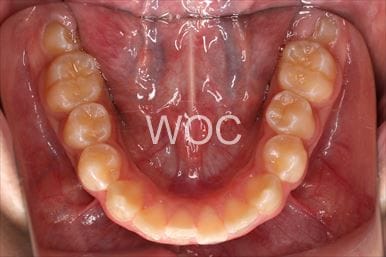

治療後1

-

治療後2

-

治療後3

-

治療後4

-

治療後5

- 年齢:22歳女性

- 主訴:出っ歯、前歯で噛み切れない

- 基本矯正料金:85万円

- 治療期間:1年4ヶ月

- 非抜歯